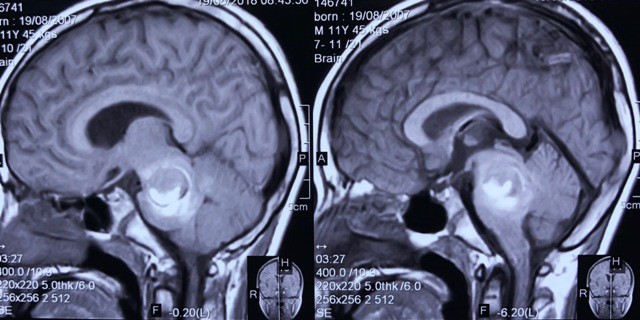

Phim chụp cộng hưởng từ khối u thân não chảy máu ở bệnh nhân.

ThS.BS Nguyễn Thanh Xuân – Phó Trưởng khoa Phẫu thuật Thần kinh I, BV Việt Đức cho biết, ngày 21/8/2018, bệnh nhân vào viện trong tình trạng lơ mơ, chậm chạp, bị liệt chân tay, mạch chậm, được chẩn đoán là một khối u mạch lớn ở thân não chảy máu, dẫn đến tình trạng bệnh diễn biến nặng nề.

Kết quả sinh thiết, bệnh nhân bị u máu thể hang chảy máu (u lành tính). Dự kiến, bệnh nhân có thể xuất viện sau 2,3 ngày nữa.